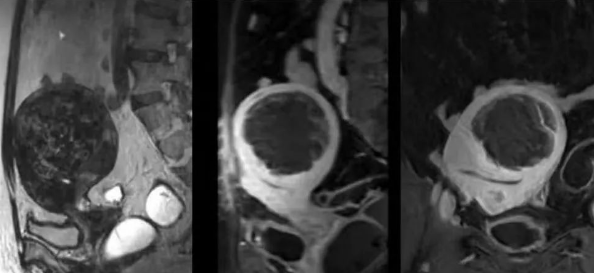

陳寶瑩主任首先給祝女士進(jìn)行了詳細(xì)的盆腔磁共振評(píng)估,發(fā)現(xiàn)子宮肌瘤比較大,直徑七公分,類型和位置都適合做磁波刀治療。陳寶瑩主任立即為她制定了個(gè)性化治療方案,并為她完成幾項(xiàng)術(shù)前檢查。

治療當(dāng)天,為緩解祝女士的緊張心情,陳寶瑩主任和她進(jìn)行了充分溝通。術(shù)前準(zhǔn)備就緒后,治療正式開始了。治療過程中,患者全程清醒,可以及時(shí)反饋治療感受。醫(yī)生也即時(shí)調(diào)整,確保整個(gè)治療安全有效,兩小時(shí)后治療順利結(jié)束,患者體驗(yàn)度好。即時(shí)評(píng)估發(fā)現(xiàn)7公分的子宮肌瘤被消融掉80%,達(dá)到了預(yù)期目標(biāo)。祝女士觀察一個(gè)小時(shí)后,沒有什么不舒服即回家了。